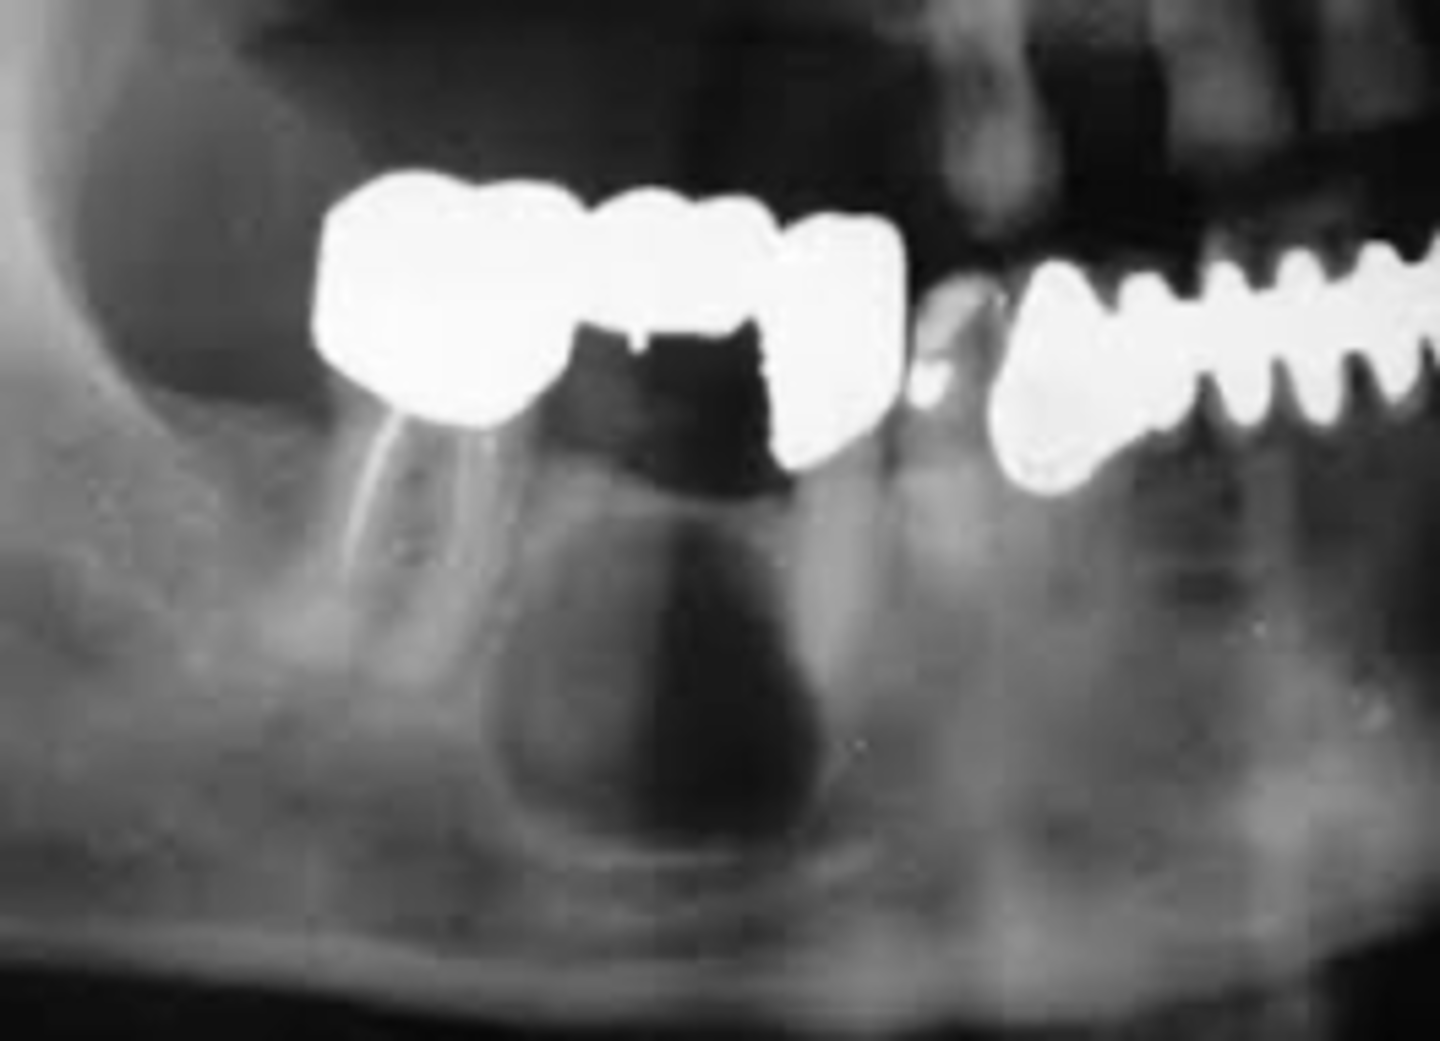

What type of cyst is a Residual Cyst?

Odontogenic, inflammatory

What is the vitality of teeth associated with Residual Cysts?

Nonvital teeth

Where is a Residual Cyst located?

Above IAN canal

What is the treatment for Residual Cysts?

Marsupialization (a surgical procedure where a cyst is opened and sutured to the surrounding tissue to create a permanent drainage pathway, preventing reformation)